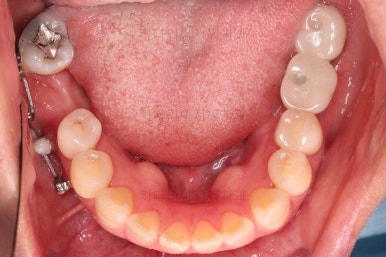

초진 시 입안의 모습입니다.

아랫니 큰 어금니 하나가 없어서 임플란트를 원하셨던 환자분이셨어요.

치아가 빠진지 오래되어 앞뒤 치아가 모두 반자리로 쓰러진 상태였어요.

그래서 큰 어금니 사이즈의 임플란트가 식립되지 못하는 상황이었어요.

이가 없는 뒤쪽 치아가 앞으로 쓰러져있고요. 맨 뒤에 사랑니까지 앞으로 쓰러져있네요.

이대로 임플란트도 못할 뿐더러 이대로 계속 지낸다면 쓰러진 치아에 계속 힘이 가해지니 치아 수명에 굉장히 안좋아요.